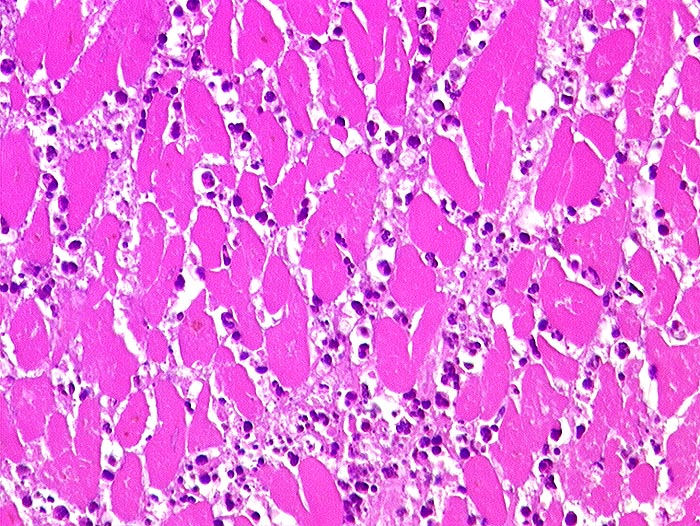

akuter Myokardinfarkt

vaskulär / Durchblutungsstörung

Herz links

Kardiovaskuläres System

Die Myozyten sind schollig zerfallen und hypereosinophil, Kernstrukturen sind nicht mehr erkennbar. Zwischen den nekrotischen Muskelfasern dichte granulozytäre Entzündungsinfiltrate.

akuter embolischer Myokardinfarkt bei Aortenklappenendokarditis.

Histologie